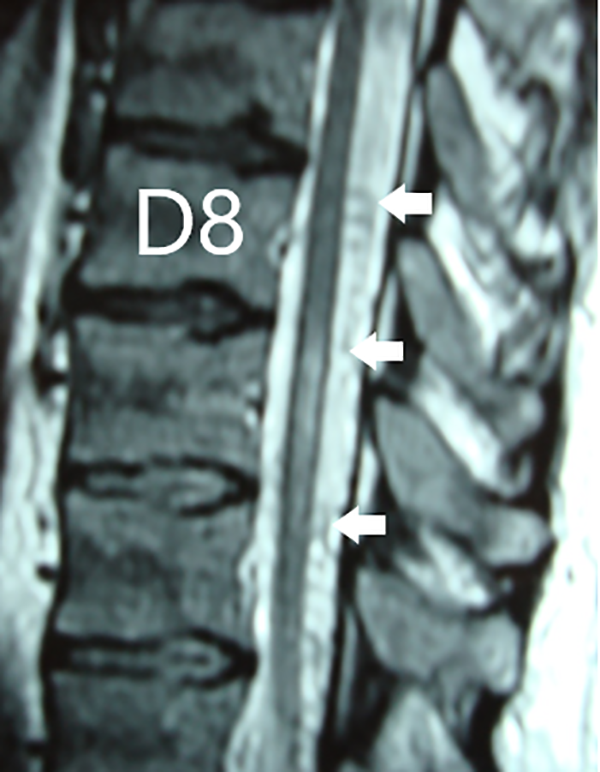

Figura 3: Caso #1. RMN sagital T2 que evidencia la hiperintensidad centromedular entre los segmentos D8-9-10 y la presencia de vasos dilatados perimedulares dorsales (flechas blancas).

CASO #1. Paciente masculino de 52 años con una historia de 6 meses de evolución de disestesias en ambos miembros inferiores, inestabilidad en la marcha, hiperreflexia y urgencia miccional. Se estudió con RMN (Fig. 3), ARM (Fig. 4) y ADM seguida de embolización con oclusión total de una FDAVE D8 izq. (Fig. 5). Evolucionó sin déficit y a los 11 meses comenzó con la misma sintomatología previa a la embolización. Se estudió nuevamente y la ADM (Fig. 6) mostraba la recidiva de la FDAVE y fue derivada para microcirugía (Fig. 7). Luego de la cirugía evolucionó sin déficit, se realizó una ADM diferida (Fig. 8) y lleva 116 meses libres de enfermedad.